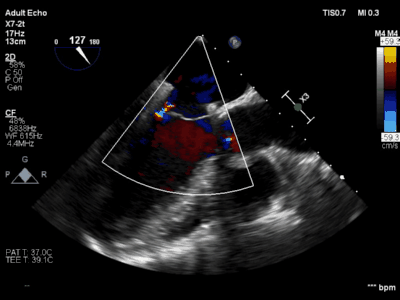

手术在厦心杂交手术室进行,患者处于全麻状态,在实时三维食道超声的指引下,心外科在患者左胸前切开4-5cm的切口,经心尖预缝荷包区域导入AMEND成形环植入系统,顺利通过二尖瓣结构中央区域进入左心房后,在体外操作AMEND系统将“D”型成型环在主动脉瓣与二尖瓣间极为狭小的空间内精确释放,并先后铆钉二尖瓣环的后叶及前叶,从而达到缩小二尖瓣环的目的(图2),这一步操作要求非常精准,稍有不慎便会损伤周围组织,引起并发症。术后即刻,患者二尖瓣反流明显减轻,达到轻度水平(图3),手术从麻醉到结束平均历时3个小时。

图3 术后超声